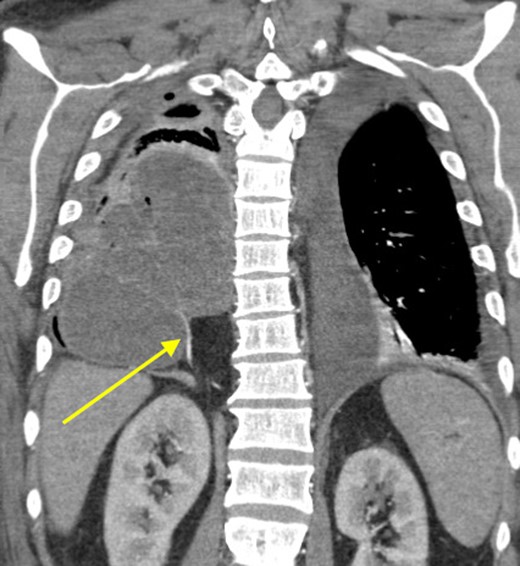

Because of the extent of this empyema, we did not carry out a video-assisted approach and proceeded immediately to a thoracotomy. We performed a thoracotomy with decortication and drainage of empyema with aspiration of ~300 ml of frank pus. The patient had no history of bleeding disorders; however, the intraoperative blood loss approached two liters. Postoperatively, the patient was very fatigued, unable to be weaned of supplemental oxygen, intermittently spiking fevers and his white blood cells (WBCs) trended in an upward direction. On the fifth post-operative day, CT scan was redone and revealed a persistent large loculated fluid collection in the right and middle lobes of his lung (Fig. 2). Interventional radiology was consulted and a 12 Fr catheter was placed into this fluid collection which drained out dark brown foul-smelling fluid. Because of the consistency of the drainage, we suspected that this patient developed an infected hematoma. On the seventh day, his condition continued to deteriorate and required pressure support. We subsequently took him back to the operating room for decortication and drainage of a suspected hematoma. In the operating room, we found two distinct large abscess pockets in the right lower lobe which we broke up and drained completely. Of note, we again encountered a lot of intraoperative bleeding loss.

Coronal view showing persistent empyema and anomalous arterial supply into sequestration.

At that time, we started to wonder if this patient had ILPS, which prompted us to scrutinize his prior CT scans. Surprisingly, we noticed an anomalous arterial supply from the right renal artery that traversed through his Bochdalek hernia and into the sequestration (Figs 2 and 3). Two days after the operation, the patient was extubated and his clinical course was relatively benign. Also, no pathogens were detected by microbiological analysis of the intraoperative cultures and bronchial lavage. Pleual biopsies from the first operation just showed some acute fibrinous pleuritis with calcium. One week later, his mental status recovered at baseline, he was breathing without supplemental oxygen and his WBCs count had normalized. The patient was discharged to rehab with follow up in the clinic to discuss surgical resection of the ILPS in order to prevent recurrent symptoms.